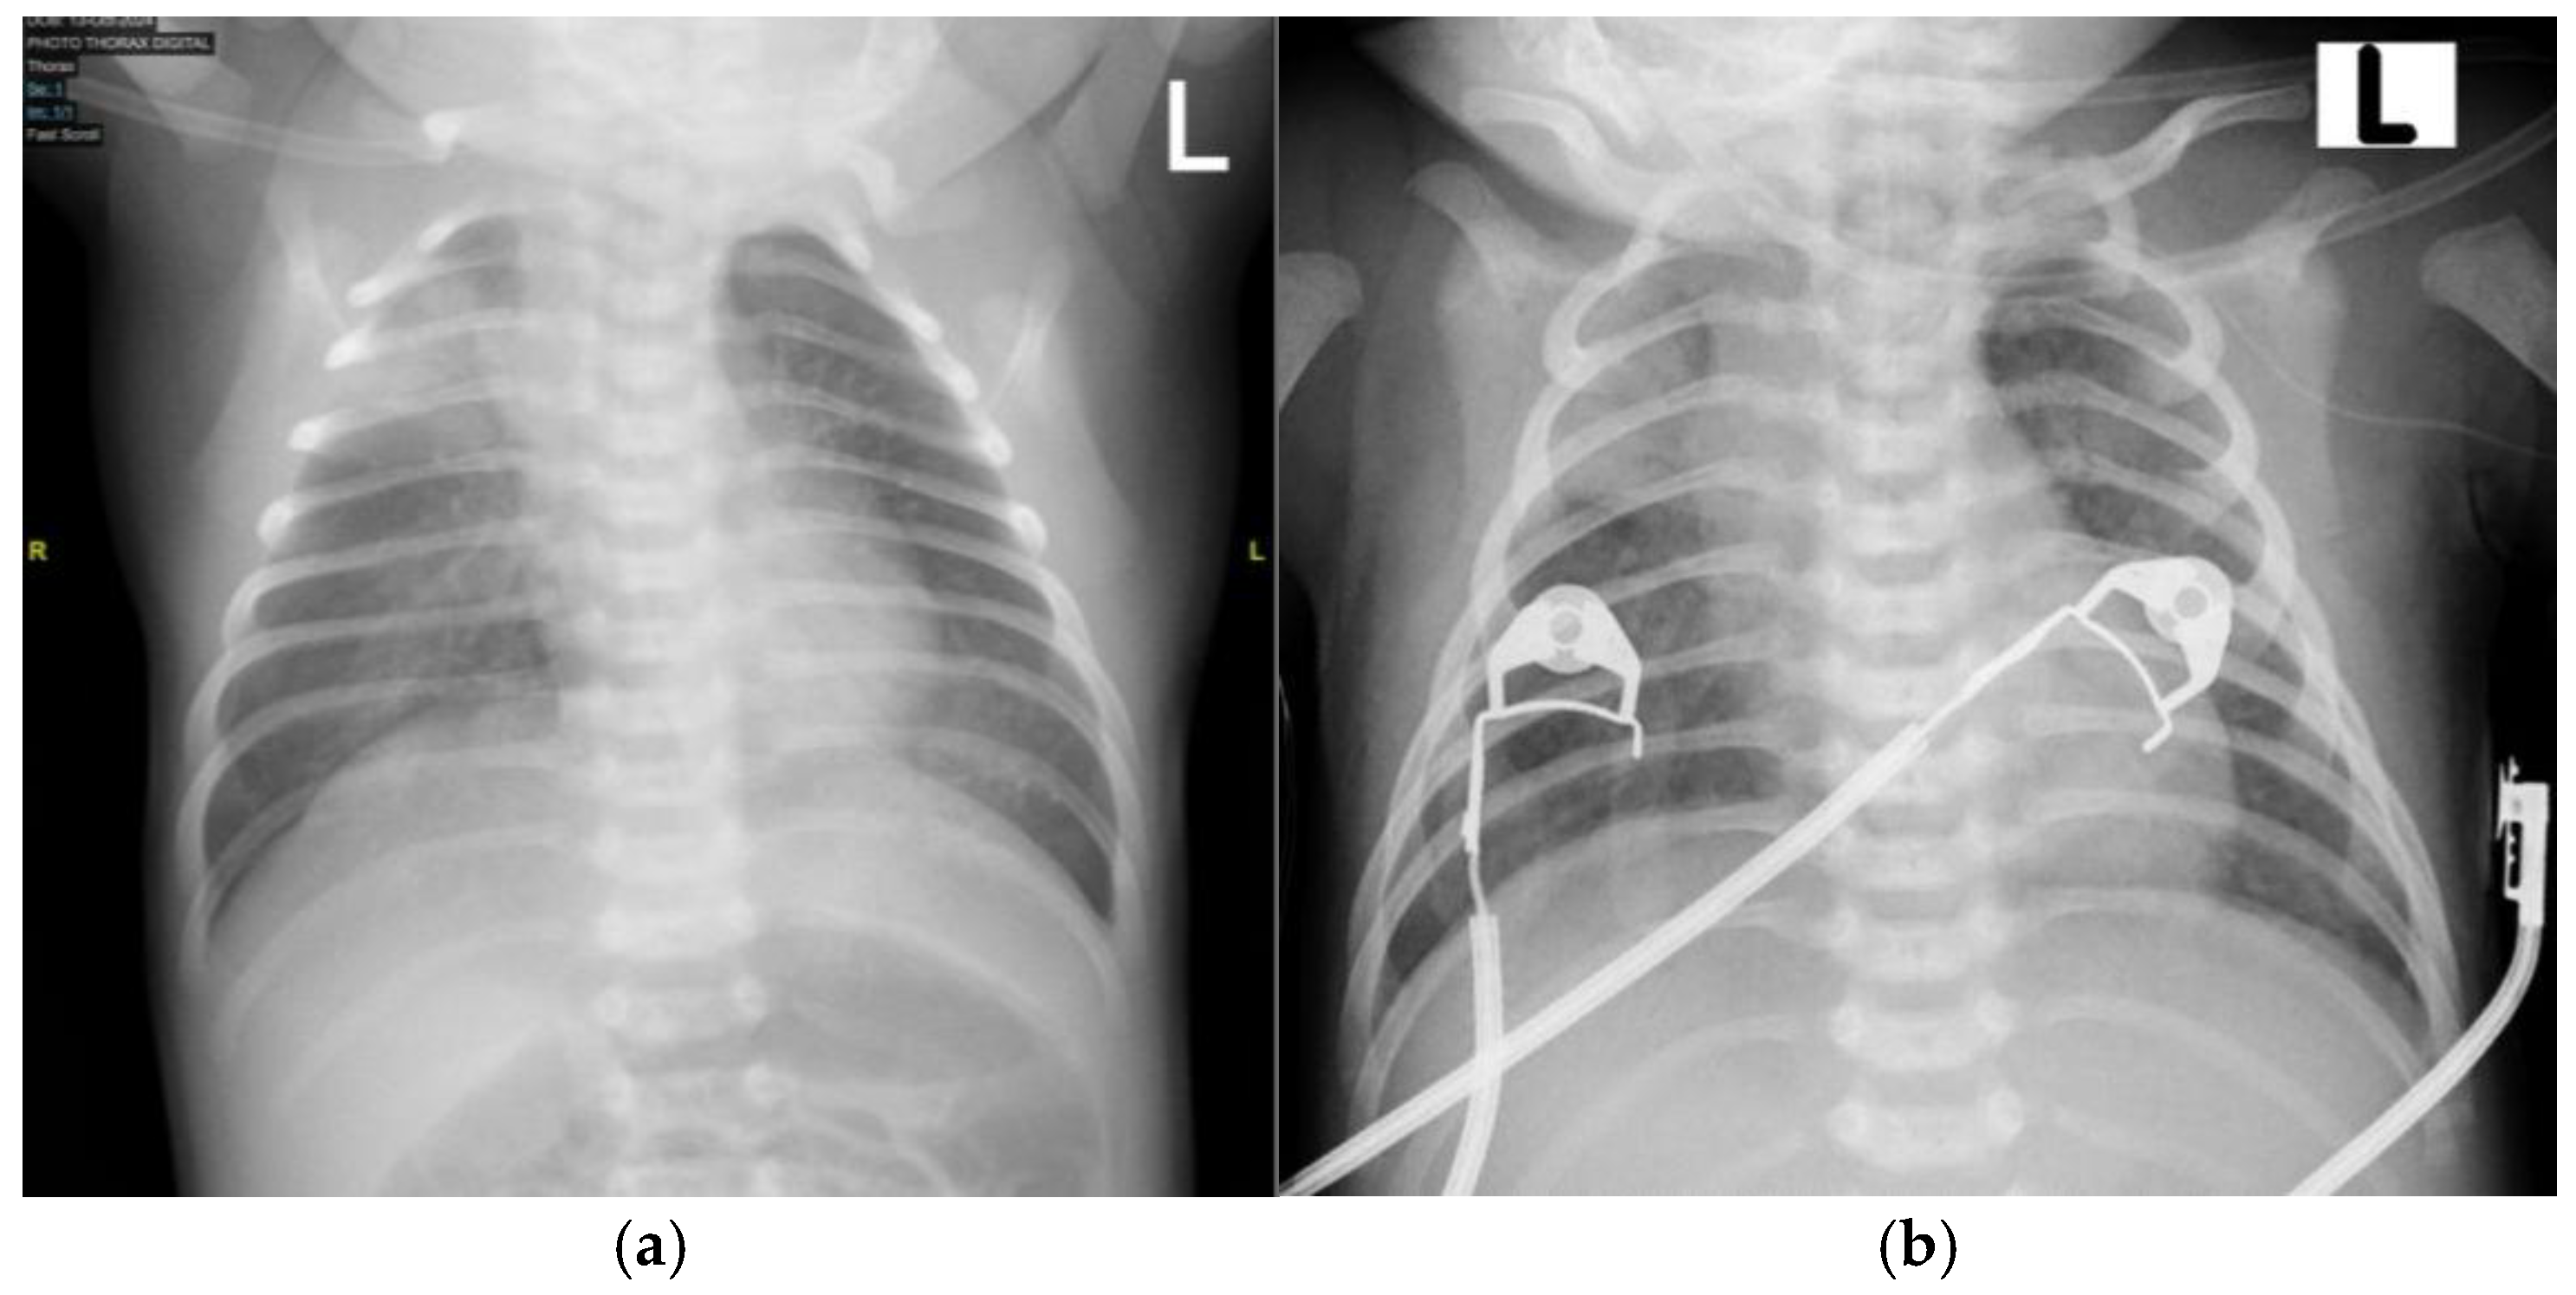

Upon initial examination, the patient exhibited respiratory distress, with grunting, subcostal chest retractions, and an SpO2 of 81% on room air. Oxygen supplementation was initiated using continuous positive airway pressure (CPAP), resulting in an improved oxygen saturation of 98%. A chest X-ray was performed, revealing pneumonia (Figure 5a). However, during monitoring, the patient’s respiratory distress worsened, with a decline in oxygen saturation and episodes of periodic apnea, necessitating intubation. The patient was subsequently transferred to the NICU for further respiratory support. Initial and follow-up blood laboratory findings are summarized in Table 2.

By day 9 in the NICU, the patient’s general condition had stabilized, and extubation was performed (Figure 5b). On day 10 of hospitalization, the patient was transferred to the neonatal high-care unit (NHCU) for continued monitoring and supportive care. The patient remained in the NHCU for an additional 5 days, during which antibiotic therapy was continued, with cefotaxime given for a total of 12 days.

Figure 5. Anteroposterior (AP) chest X-ray showing (a) bilateral pneumonia on admission to the emergency department (ED) and (b) improvement in pneumonia on day 9 of hospitalization before extubation. “L”: an anatomical marker indicating the left side.